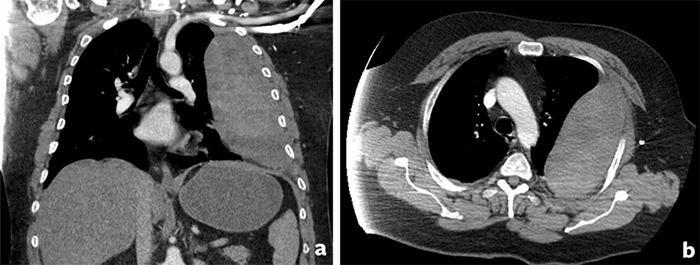

A 47-year-old man with a past medical history of hypertension on lisinopril and supraventricular tachycardia controlled with metoprolol and no history of blood thinning medications suffered a fall from standing and landed on his left side. He was initially managed at an outside hospital and discharged home with pain medications and a chest wall contusion diagnosis with no further evidence of worsening pulmonary function. A chest radiograph was performed as part of the workup that did not show any evidence of acute intrathoracic pathology (Figure 1).

Figure 1. Chest radiograph from the initial presentation at the outside hospital taken 48 hours before re-presentation.